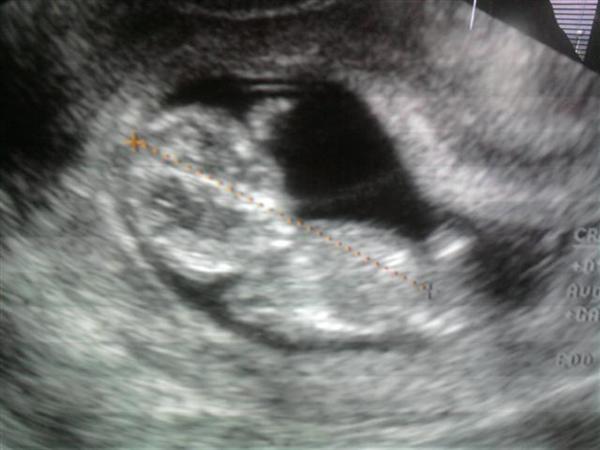

Felhívtam még 9 körül S. dokit, azt mondta jó lenne ha jövő héten megnézne valaki, de ha kibírom 5-ig, akkor majd ő. Elkértem barátnőm dokijának a számát és azt mondta ma 13 h-ig bármikor mehetek. Már haza is értem tőle. Megvolt a baba, pulzált a kis szíve, de szerinte nem felel meg 6 hetesnek, csak 5 hetesnek. Kicsit gondterhelt volt a tekintete, azt mondta ne nézegessem az uh képeket, az a lényeg, hogy van pulzálás.

Vegyes érzésekkel jöttem el tőle emiatt a kisebb méret miatt, de azért az sokat segít a nyugalmamon, hogy a tegnapi vérzés nem okozott túl nagy galibát. Remélhetőleg később sem lesz gond.